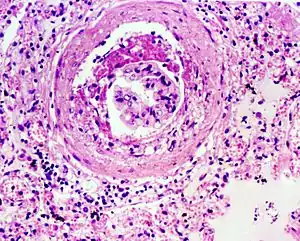

Glomerulosclerosis is the hardening of the glomeruli in the kidney. It is a general term to describe scarring of the kidneys' tiny blood vessels, the glomeruli, the functional units in the kidney that filter urea from the blood.

Proteinuria (large amounts of protein in the urine) is one of the signs of glomerulosclerosis. Scarring disturbs the filtering process of the kidneys and allows protein to leak from the blood into the urine. However, glomerulosclerosis is one of many causes of proteinuria. A kidney biopsy (the removal of a tiny part of the kidney with a needle) may be necessary to determine whether a patient has glomerulosclerosis or another kidney problem. About 15 percent of people with proteinuria turn out to have glomerulosclerosis.